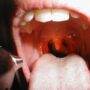

Зато забеременев во второй раз, я прочувствовала все эти тяготы в полной мере: меня тошнило, рвало, еда в рот не лезла, да еще разболелось горло. Для меня ангина не редкость, еще в детстве врач поставил диагноз «хронический тонзиллит», с тех пор регулярно 1-2 раза в год воспаляются миндалины.

Боль ужасная, невозможно даже проглотить слюну. Я привыкла пользоваться пастилками или спреями от боли в горле, но большинство из них запрещено в 1-м триместре беременности, да еще в них содержатся ароматизаторы и красители.